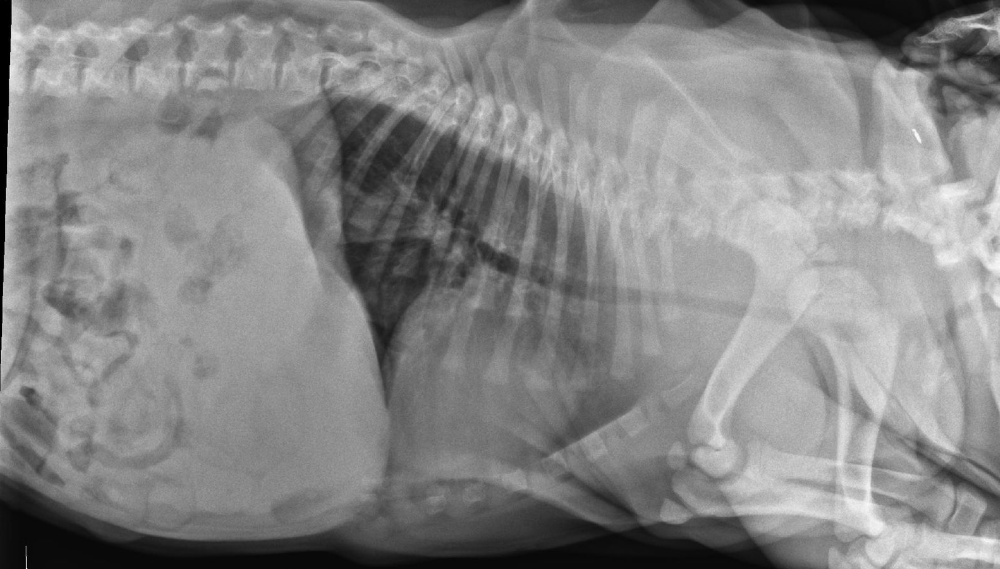

Asi neexistuje domácí lékárnička, ve které by se nenašel nějaký paracetamol, například v lécích na bolest hlavy nebo na chřipku. Někteří chovatelé ve snaze pomoci svému mazlíčkovi doslova riskují jeho život tím, že mu podají léky určené lidem. Paracetamol je pro kočku i psa vysoce toxický. Otravy bývají časté vzhledem ke snadné dostupnosti léčiv.